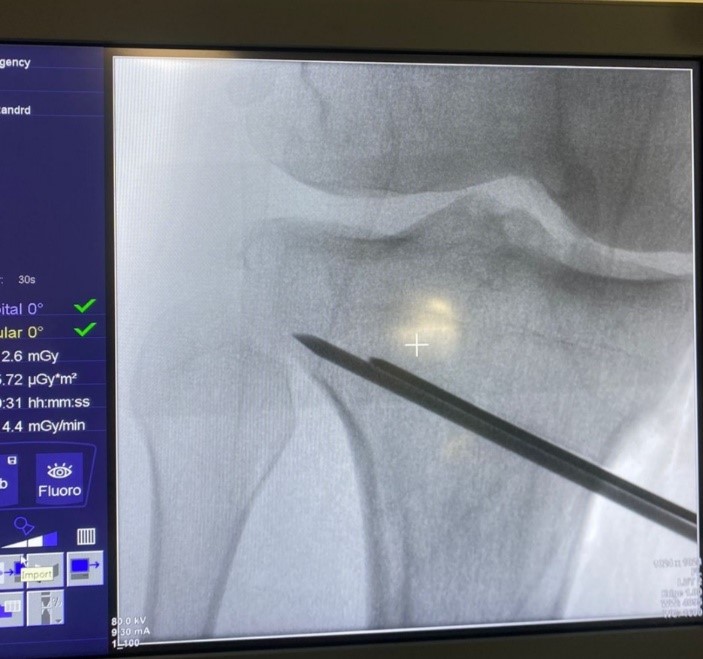

En todos los pacientes se indicó una RNM de rodilla (Magnetom 1.5T, Siemens) para descartar lesiones meniscales y ligamentarias asociadas y evaluar el estado de las superficies articulares de los tres compartimentos de la rodilla. Todas las cirugías se realizaron por un mismo equipo quirúrgico, en un mismo quirófano y en todas se utilizó el mismo intensificador de imágenes de alta resolución (Cios Alpha, Siemens).

En todos los pacientes se practicó una artroscopia de rodilla (Fig. 1) antes de la osteotomía proximal de tibia para poder evaluar el cartílago del compartimento medial y lateral, así como la existencia de lesiones meniscales asociadas. Las lesiones del cartílago articular fueron estratificadas según la clasificación de Outerbridge17. En caso de lesiones de cartílago de gran extensión, se hicieron nanofracturas.

Mediante una incisión oblicua en cara anteromedial de la pierna se expuso la cara medial del tercio proximal de la tibia y liberación del ligamento colateral medial. Posteriormente, bajo visión directa con el intensificador de imágenes, se colocó una clavija desde medial, con dirección al tercio superior de la articulación tibioperonea proximal para marcar la localización del corte de la osteotomía (Fig. 2). Se realizó luego una osteotomía incompleta, que en el plano sagital debe ser paralela al slope tibial y sin afectar la cortical lateral de la tibia. Se inició el corte con sierra oscilante y se finalizó mediante escoplos. Luego de esta última, se procedió a su apertura gradual (Fig. 3). Una vez lograda la corrección planificada, se colocó una placa tipo Puddu, con los dos tornillos proximales para esponjosa, de 6.5 mm de diámetro y dos tornillos distales bloqueados, de 4.5 mm de diámetro (todas las placas fueron fabricadas en Argentina). Fijada adecuadamente la osteotomía, se rellenó la brecha de apertura con injerto óseo autólogo o alógeno liofilizado, mezclado con 1 g de vancomicina en polvo (Fig. 4). La colocación de la placa lo más cercana a la cortical posterior de la tibia tiene por objetivo tratar de evitar el incremento del slope tibial (Fig. 5).

Figura 2.Colocación de clavija medial y corte paralelo con sierra